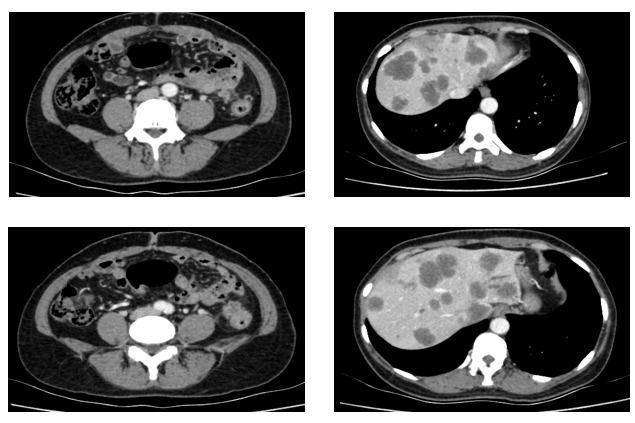

患者为51岁女性,因“间断腹痛半年余,进行性加重1月”于2021年3月就诊于我院结直肠外科。入院时胸全腹部CT(2021-3-29)提示:降结肠远端增厚,肝内多发占位,肺内多发小结节,考虑转移。肠镜检查:在距肛门28公分处,管腔狭窄,内镜不能通过。病理提示:腺癌。

于2021.04.17行“FOLFOX6”方案化疗1周期,行“奥沙利铂”化疗时,出现严重过敏。因患者基因状态为RAS,BRAF野生型,第2周期始给予“FOLFIRI+西妥昔单抗”,在治疗过程中,肿瘤标志物持续下降,影像学也显示肝脏病灶明显缩小。疗效评价PR,在2021-09-25在局麻DSA下行“肝动脉造影并化疗灌注栓塞术”。

2022-09-07至2023-01-03院外使用DS-8201治疗5周期。2周期后疗效评价:PR。CT示:腹膜后淋巴结较前部分缩小;双肺多发转移灶较前缩小。

残余病灶的手术切除:2023-02-22至外院行“左半肝切除术,尾状叶切除术,肝段切除术,胆囊切除术,腹腔淋巴结清扫术,肠粘连松解术,肾周围粘连分解术,肝脏肿物射频消融,肝动脉结扎,腔静脉损伤修复术”。